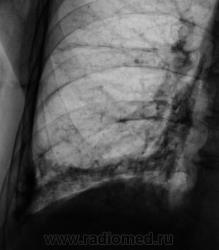

Пациент направлен на рентгенографию ОГК.

А томограмм нет. Просто демонстируется обызвествленная плевра.